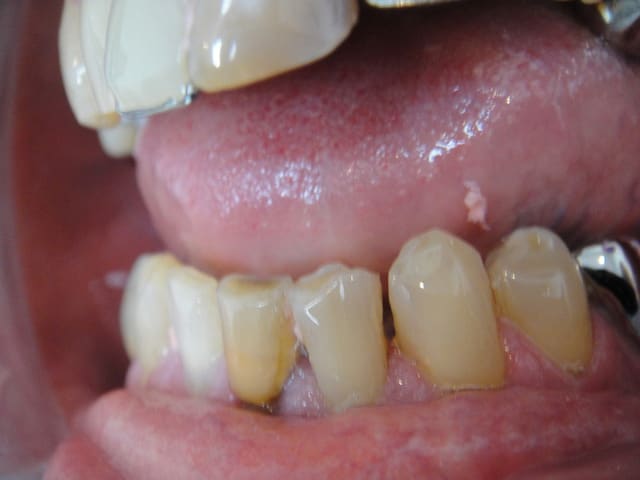

patient de 70 ans qui ne souhaite pas d'implant.

pas de parafonction à signaler ni de demande esthétique importante.

32 et 42 sont parodonto solides.

prendriez vous les canines?

ça ne me parait pas indispensable.